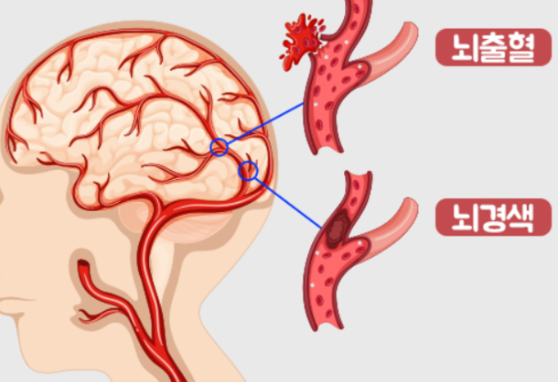

뇌경색은 뇌세포가 죽어가는 과정으로 즉시 치료하지 않을 경우 생명을 앗아갈 수 있는 치명적인 질환 중 하나입니다. 뇌졸중 종류 중 하나인 뇌경색은 뇌혈관이 막혀 뇌에 혈액순환이 제대로 이루어지지 않아 발생하는 증상인데요.

뇌졸중이 심각해지면 뇌 벽 내부의 약한 부분이 터져 뇌 안에 출혈이 생기기 때문에 미리 예방하고 빠르게 처치하는 것이 매우 중요합니다. 때문에 뇌경색 초기 증상이 의심된다면 빠르게 가까운 병원으로 가보는 것을 권장드립니다.